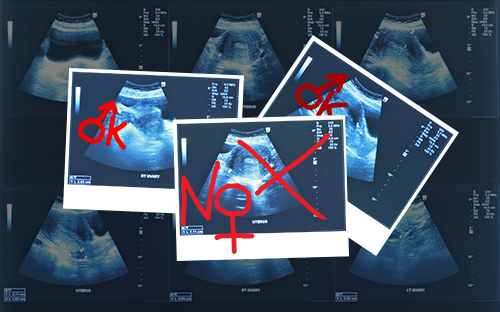

The Indian Minister for Women and the Development of Childhood “has suggested making prenatal gender testing mandatory in order to reduce the high level of female foeticides”.

Such tests are currently banned in India and carry a five-year prison sentence. This measure is aimed at “preventing female abortions by parents who only wish to have a boy”. However, the Minister in question, Manka Gandhi, thinks the opposite and believes that it would be “more effective” to establish the gender of the foetus from the start of pregnancy. “We have to change the current policy,” she explained, “every pregnant woman should have the right to know whether she is carrying a boy or a girl”. Furthermore, “every pregnant woman should be registered and followed up until the end of pregnancy to establish whether or not she gave birth and what happened”.